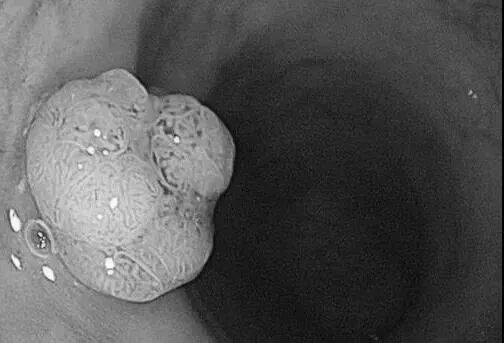

直肠管状腺瘤

而检查结果令人吃惊:14人全部发现息肉(全部是腺瘤),大肠癌的前身90%是肠息肉演变的,其中确诊直肠癌合并息肉1例。

换句话说,14个肠镜中13个有癌前病变,1个确诊肠癌!